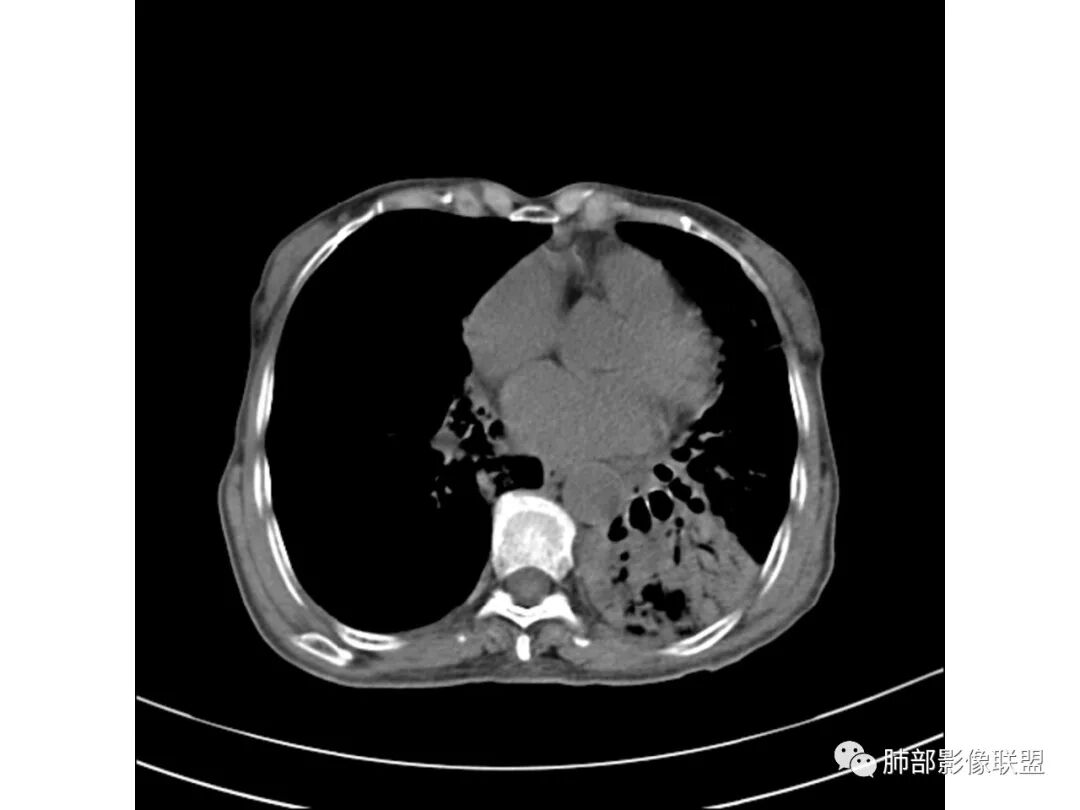

这些应该是胸水

支气管扩张、扭曲成团,附近钙化灶

肿瘤会这样吗?

宇宙星空

一般不会

纵膈也左移了

这例左下叶的体积是整体缩小的,左下叶的支气管主干稍微小一点点,然后左上叶的下舌段也有类似的病灶,然后我们看到一团乱的支气管扩张,但它有特点,边缘凹凸不平。那什么样的支气管扩张边缘会如此凹凸不平呢,等我截个图:

看最后一幅图,上面这个支气管,有可能是淋巴瘤,为什么?他的支气管稍扩张,直达远端、实变。

首先这幅图支气管很多地方是扭曲的,远端扩张的特别厉害。如果是肿瘤,首先考虑淋巴瘤,因为支气管可直达远端,稍扩张,但是它的前提是周围要实性占位的,而且它不会这样扭曲变形。我们看这个病例的支气管扩张,它支气管扩张占大部分区域,中间稍有些实性的结构,这就不符合了。这幅图你会发现所有支气管都是扩张的,实性部分偏少,外围胸水。所以我更倾向慢性炎性病变,能够引起支气管扩张的炎性病变有哪些?结核?NTM?支扩伴感染?大方向是慢性炎性病变。这些左下肺播散出来的病灶,咳中等量黄浓痰,我考虑还可能合并细菌感染。